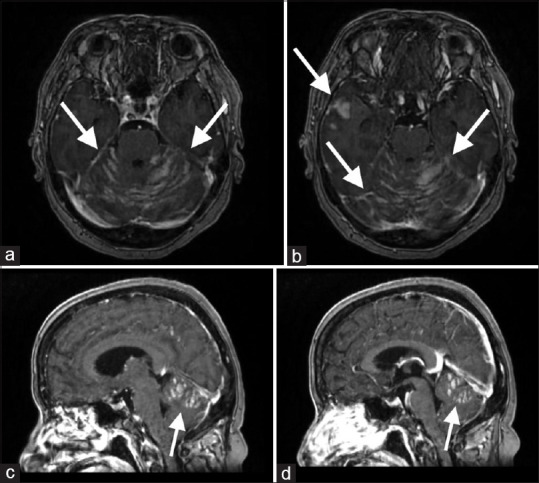

Sugar-Coating or Zuckerguss Appearance on Magnetic Resonance Imaging in Leptomeningeal Carcinomatosis in a Patient with Acute Myeloid Leukemia.